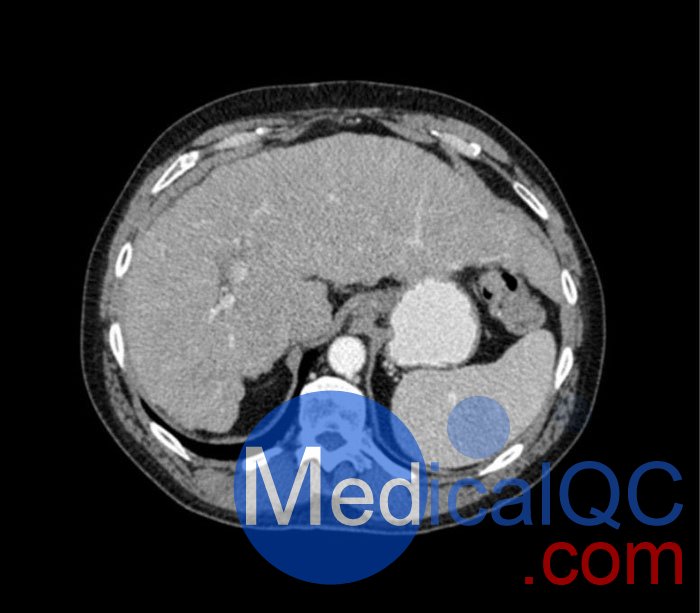

WEK53-04肝硬化腹部模體,WEK53-04門靜脈期腹部模體詳細(xì)介紹:

WEK53-04肝硬化腹部模體,WEK53-04腹部模體模擬了門靜脈期的造影劑增強(qiáng)腹部。它覆蓋了第十胸椎至第三腰椎。

WEK53-04肝硬化腹部模體,WEK53-04腹部模體代表膽囊切除術(shù)后的腹部,帶有小夾子。肝臟有肝硬化的典型體征,在第三腰椎水平植入下腔靜脈過濾器。兩個(gè)腎臟都有囊性病變,左側(cè)有一小塊腎結(jié)石。

該模型可用于 CT(包括 CBCT)以評(píng)估和優(yōu)化成像性能和后處理應(yīng)用,包括支持 AI 的應(yīng)用。它也適用于培訓(xùn)目的。

該模型提供了對(duì)軟組織和骨組織的詳細(xì)而逼真的模擬??障吨刑畛渲s-160HU的纖維素-聚合物復(fù)合材料。

WEK53-04肝硬化腹部模體,WEK53-04門靜脈期腹部模體診斷特征

真實(shí)模擬脈管系統(tǒng)、骨骼和軟組織,包括肝臟、胰腺、脾臟、腎上腺、腎臟、胃、小腸和結(jié)腸。

• 肝硬化

• 膽囊切除術(shù)

• 下腔靜脈濾器

• 腎囊腫

• 腎結(jié)石

• 淋巴結(jié)腫大

WEK53-04肝硬化腹部模體,WEK53-04門靜脈期腹部模體產(chǎn)品成像圖: